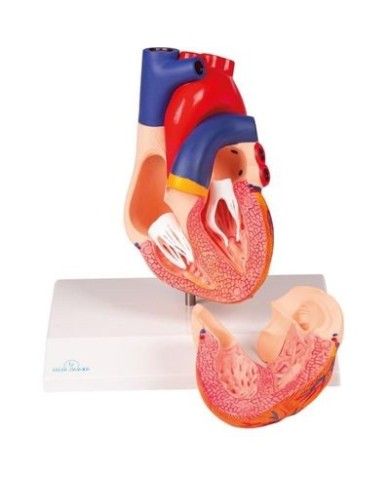

La parete anteriore del cuore è staccabile per poter vedere i ventricoli.

Modello anatomico di cuore, ingrandito 2 volte, su cavalletto

Questo modello dettagliato mostra, oltre alle strutture anatomiche del cuore, anche una parte del diaframma (base)